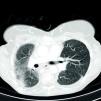

High-resolution thoracic contrast computed tomography (CT) (Figure 3) revealed extensive venous collateral circulation due to obstruction of the superior vena cava, together with marked right pulmonary apical fibrosis and mediastinal deviation to the right. There was minimal space between the posterior face of the sternum and vascular structures (particularly the origin of the supra-aortic trunks at no more than 3 mm) which were in contact with the aortopulmonary window and the right ventricular free wall. The subxiphoid region was in contact with the anterior face of the left hepatic lobe.

Following confirmation by CT of the patency of vascular access via the inferior vena cava, it was decided to perform PPM implantation via the right femoral vein.